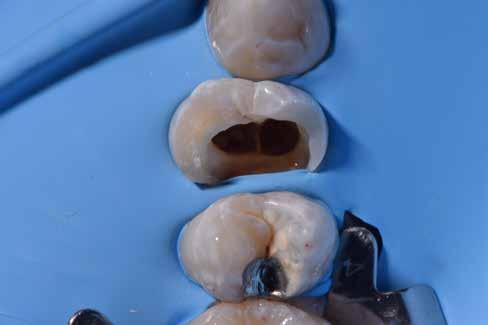

Az európai uniós rendeletekkel való harmonizáció keretében új szakvizsgák, feltételek, követelményrendszer alakult ki a hazai sztomatológiában. Megjelent az új orális implantológia szakvizsga, és egészen új szintre került a többi fogászati szakorvosi vizsga követelményrendszere is. Az új szakvizsgákhoz tartozó követelmények egyben a szakma új szabályainak is tekinthetőek, vagyis jelentős feladat elé állítják a rendelőket. A fejlődést a páciensek is nyomon követhetik az interneten keresztül, és ezzel új, és a réginél sokkal magasabb igényszintű fogászatot, implantológiát elvárásként fogalmazhatják meg. Ha ezt az új színvonalat, a fejlődést kevéssé követő fogorvosi rendelővel szemben várják el, akkor az ott végzett kezelések után kialakulhat a „konfliktus szituáció.” (1–3. képek)

Az implantológiában inkább a szájsebészeti jellegű témák voltak hangsúlyosak, a manuális eljárások dominanciája volt jellemző. Ma inkább a különleges csontpótlásokról, az előre megtervezett fogpótlásból (backwards planning = visszafelé tervezés) kiindult sebészeti tervezésről esik sok szó, ez vált követelménnyé. A digitális eljárások fölénybe kerültek a manuálisokkal szemben. A régi technológiák folyamatosan kikopnak a gyakorlatból. És itt is kérdés: Mi az, ami megfelel – még vagy már – a szakma szabályainak? Már csak emiatt is sok mindent újra kell gondolni (4–5. képek)